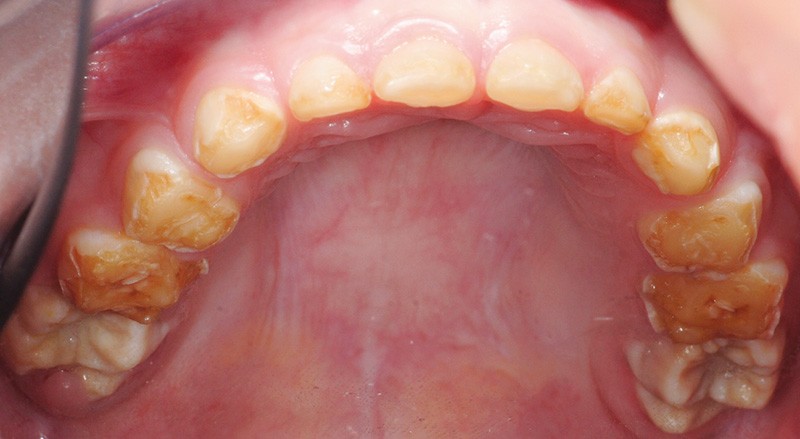

(fig. 2 et 3)

Il s’agit de l’amélogénèse imparfaite héréditaire, qui :

• touche toutes les dents de l’arcade ;

• entraîne une coloration jaune orangée de l’émail sur toute la surface coronaire ;

• est liée à une étiologie génétique.